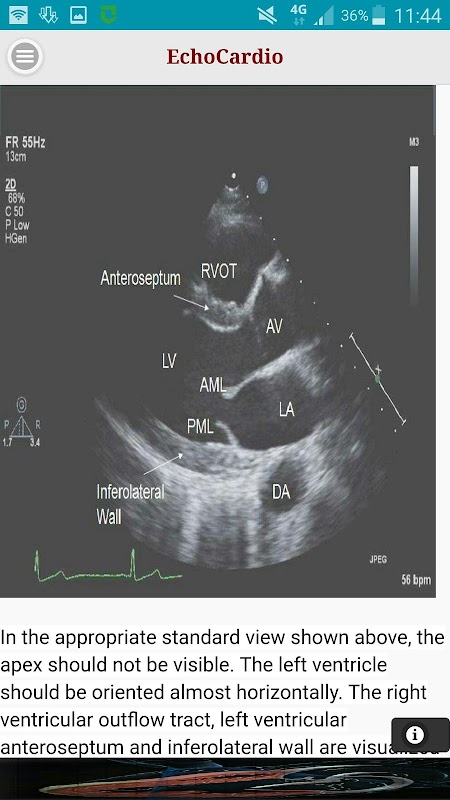

Parasternal lange as